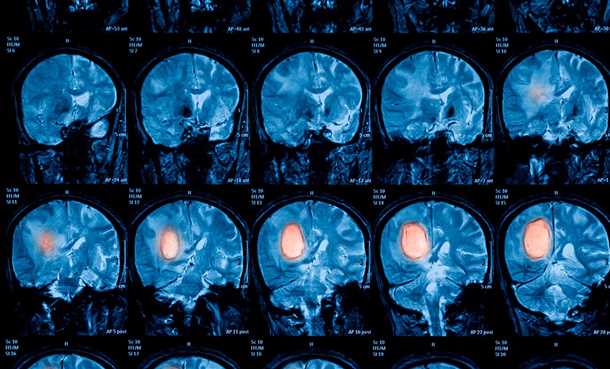

Роль Магнитно-резонансной томографии (МРТ) в выявлении воспалительных и пораженных сосудистых образований мозга

Преимуществами МРТ являются высокая разрешающая способность и возможность получать изображения мягких тканей с высокой контрастностью. Этот метод позволяет обнаруживать изменения в структуре и функции сосудов мозга, такие как воспалительные процессы, нарушения кровообращения или аномалии развития.

Магнитно-резонансная томография (МРТ) проводится с использованием магнитного поля и радиоволн. Наблюдаемое в результате исследования изображение головного мозга оказывается под воздействием различных физических параметров, что позволяет определять отличительные особенности сосудистых образований и тканей мозга, а также выявлять патологические изменения.

В МРТ можно использовать конtrastные вещества для повышения контрастности изображения. Это позволяет выявить наличие опухолей, кровотечений, воспалительных очагов и других изменений в сосудах головного мозга. Благодаря применению МРТ, врачи имеют возможность точно определить расположение и размер сосудистых аномалий, а также выяснить их влияние на работу и состояние мозга.

Таким образом, Магнитно-резонансная томография (МРТ) является эффективным методом диагностики поражений сосудов головного мозга. Ее преимуществами являются высокая точность, возможность получения подробного изображения и выявления изменений в структуре и функции сосудов мозга. МРТ с использованием контрастных веществ позволяет выявить наличие воспалительных, пораженных или измененных сосудистых образований, что помогает врачам выбрать оптимальный метод лечения и контролировать эффективность проводимой терапии.